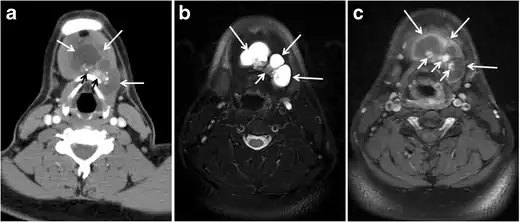

The likelihood of positive anatomic imaging is greater when serum Tg is >10 ng/mL. A diagnostic CT scan adds additional value to neck US in detecting central compartment macro-metastases in the mediastinum and retro-tracheal area. According to the recent American Thyroid Association guidelines, an upper chest and neck CT scan with IV contrast should be obtained when: 1) neck US is inadequate in visualizing possible local nodal disease (high Tg, negative neck US, and RAI imaging); 2) US is not able to delineate the disease completely, as in the case of bulky recurrent nodal disease; or 3) evaluation of possible recurrent invasive disease is needed (Figs. 7, 88 and and9).9). CT scans are also the most sensitive diagnostic tool for the detection of pulmonary micro-metastases. Many of the neck US features that are considered as suggestive signs of disease recurrence are also applicable to CT examination. These signs might include sizable rounded nodules in the thyroid bed, fine calcifications, or cystic change.[1]